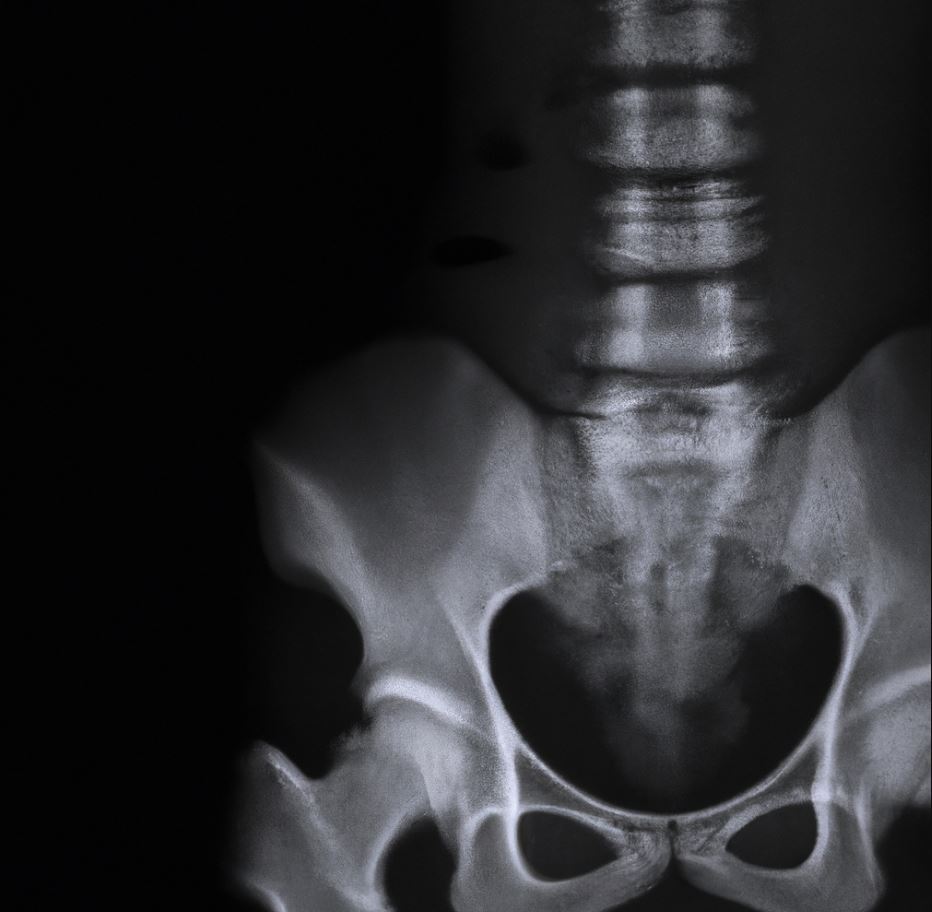

골다공증 예방하는 식습관

골다공증은 뼈의 밀도가 감소하여 뼈가 취약해지는 질환입니다. 이러한 상태를 예방하고 개선하기 위해서는 올바른 식습관을 유지하는 것이 중요합니다. 아래는 골다공증을 예방하기 위한 식습관에 대한 일반적인 지침입니다.